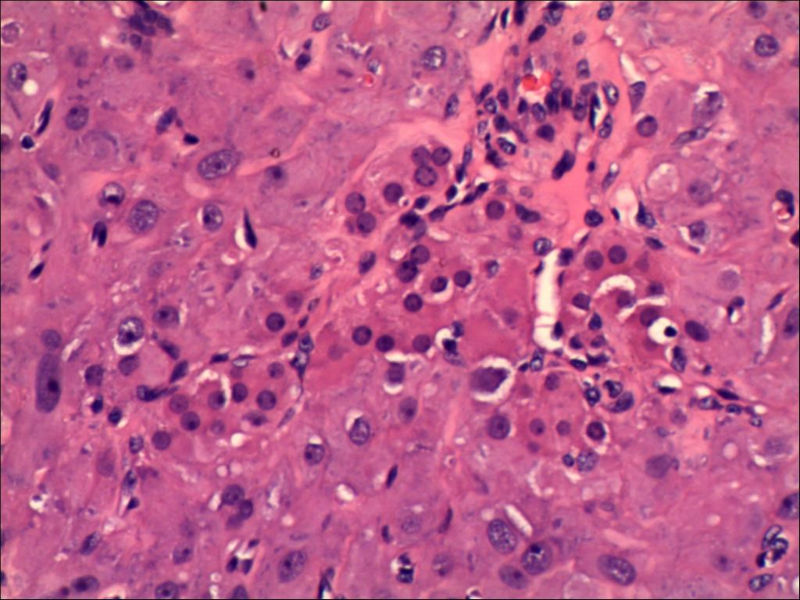

女,27岁,送检右侧卵巢肿物(另外还送检左侧卵巢肿物,大体及镜下显示为畸胎瘤),卵圆形,大小2×1×1cm,似有包膜。卵巢肿物图1

卵巢畸胎瘤中正常卵巢的黄体组织,铺砖样排列,胞浆宽大,较典型。

不好意思,可能是我没说清楚,患者对侧卵巢是畸胎瘤,不是同一侧的,我初步考虑门细胞瘤,图21,22,24,25,26中央的一些细胞是不是很像门细胞

谢谢大家的回答和解疑,忘记一个重要的病史,就是该女性为产妇。但是妊娠黄体瘤与类固醇细胞瘤怎么鉴别呢

那应该是妊娠黄体/黄体瘤,类固醇细胞瘤有嗜酸细胞和组织细胞样细胞两种,此例显然不是。